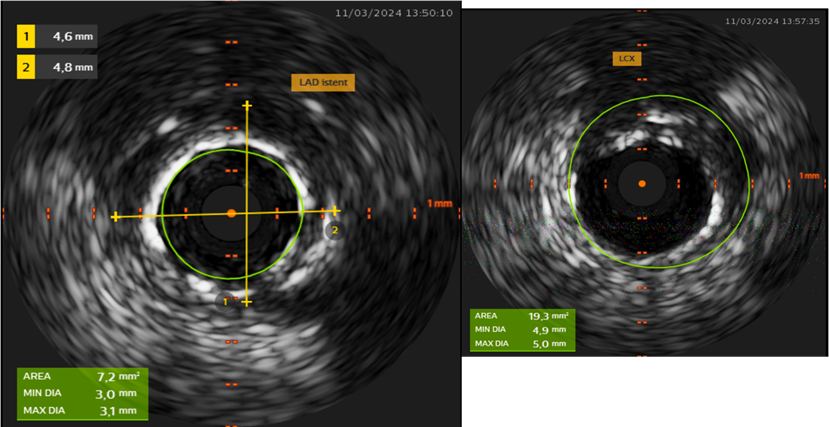

Ειδικότερα, η ενδοαγγειακή υπερηχογραφία χρησιμοποιεί υπερηχητικά κύματα που εκπέμπονται από έναν καθετήρα τοποθετημένο εντός του αγγείου. Στόχος της μεθόδου είναι η  δημιουργία εικόνων του αγγειακού τοιχώματος και των αθηρωματικών πλακών.

Η μέθοδος αυτή επιτρέπει:

• την εκτίμηση του βαθμού στένωσης.

• της σύστασης της αθηρωματικής πλάκας

• της επάρκειας τοποθέτησης ενός stent μετά από αγγειοπλαστική.

ΙVUS